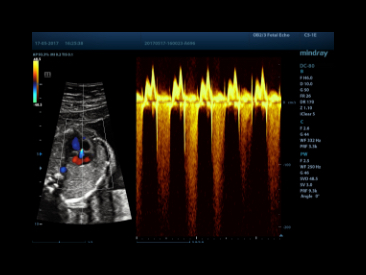

eXceptional Intelligence

Intelligence throughout entire workflowSmart OB

Auto measurement of fetal parameters: trace and calculate the BPD, OFD, HC, AC and FL on a single click.

Smart NT

Auto-trace tube cavity edge with measurement result.